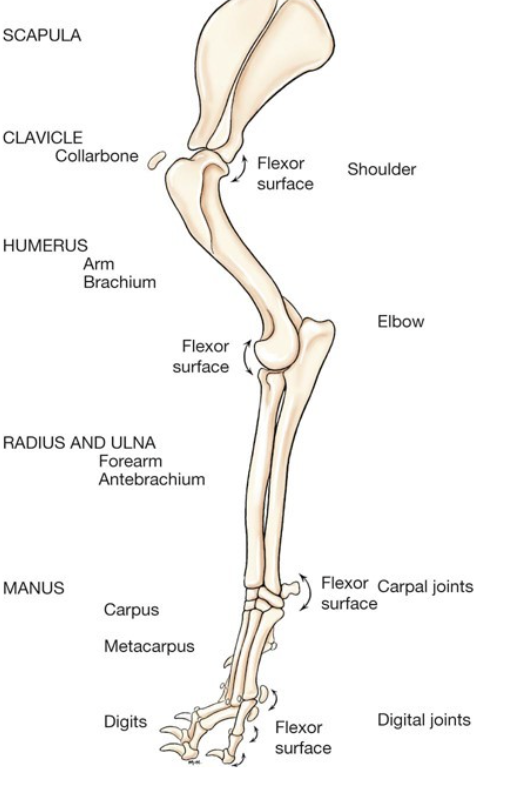

Label the diagram

A